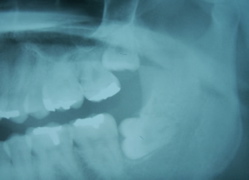

症例3

30代前半の男性です。赤矢印を見てください。親知らずのせいで、手前の歯が神経まで虫歯になってます。もっともっと前に抜くべきでした。

2分割して抜歯してます。実質抜歯時間(麻酔時間をいれずに)は7分です。2針縫ってます。